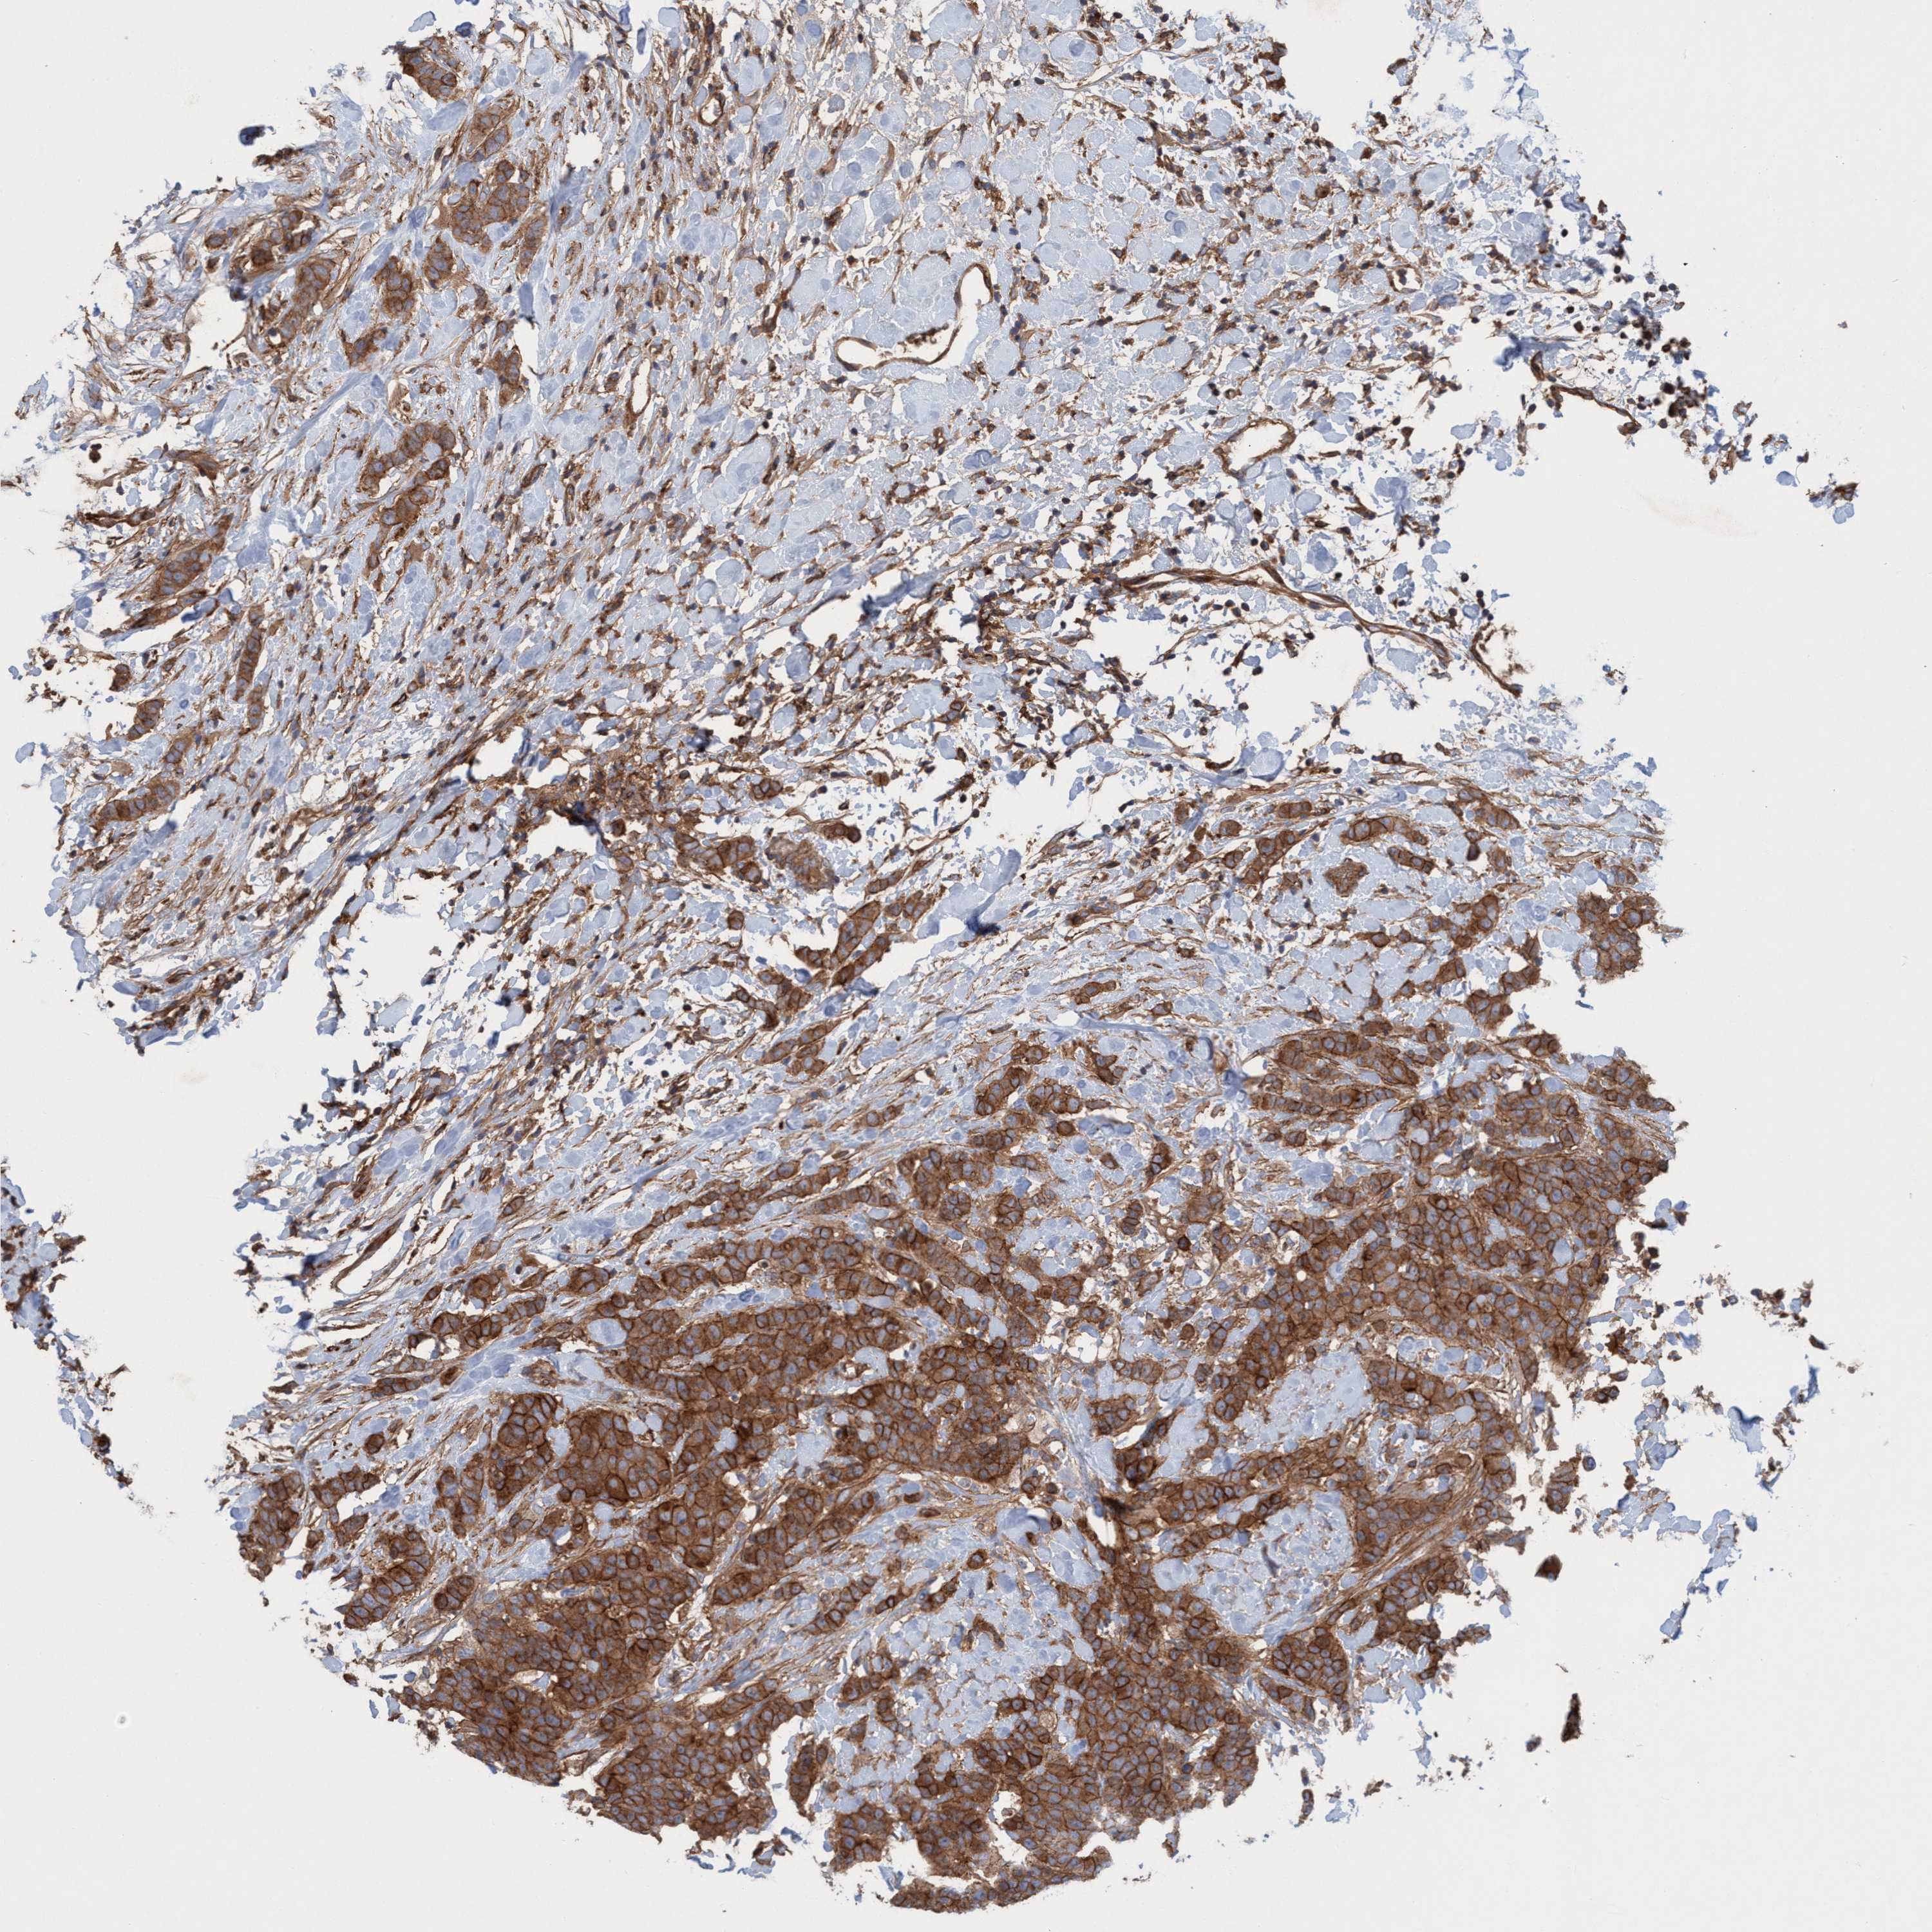

CANCER BREAST CANCER Show tissue menu

BRCA TCGA BRCA VALIDATION PROTEIN EXPRESSION

Breast cancer

Breast invasive carcinoma

SPECC1 is not prognostic in Breast Invasive Carcinoma (TCGA)